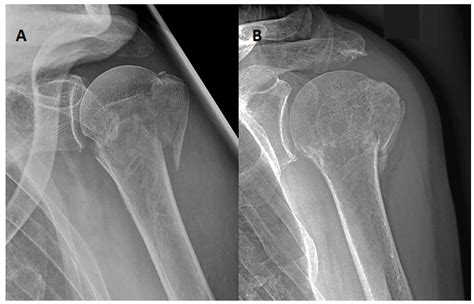

Proximal humerus fractures are classified based on the location and pattern of the fracture. The most common classification systems include:

• Neer Classification: This system categorizes fractures based on the number of parts involved (one, two, three, or four parts).

• AO/OTA Classification: This system uses a more detailed coding system to describe the fracture pattern and severity.

Understanding the classification of the fracture helps healthcare providers determine the appropriate treatment plan.